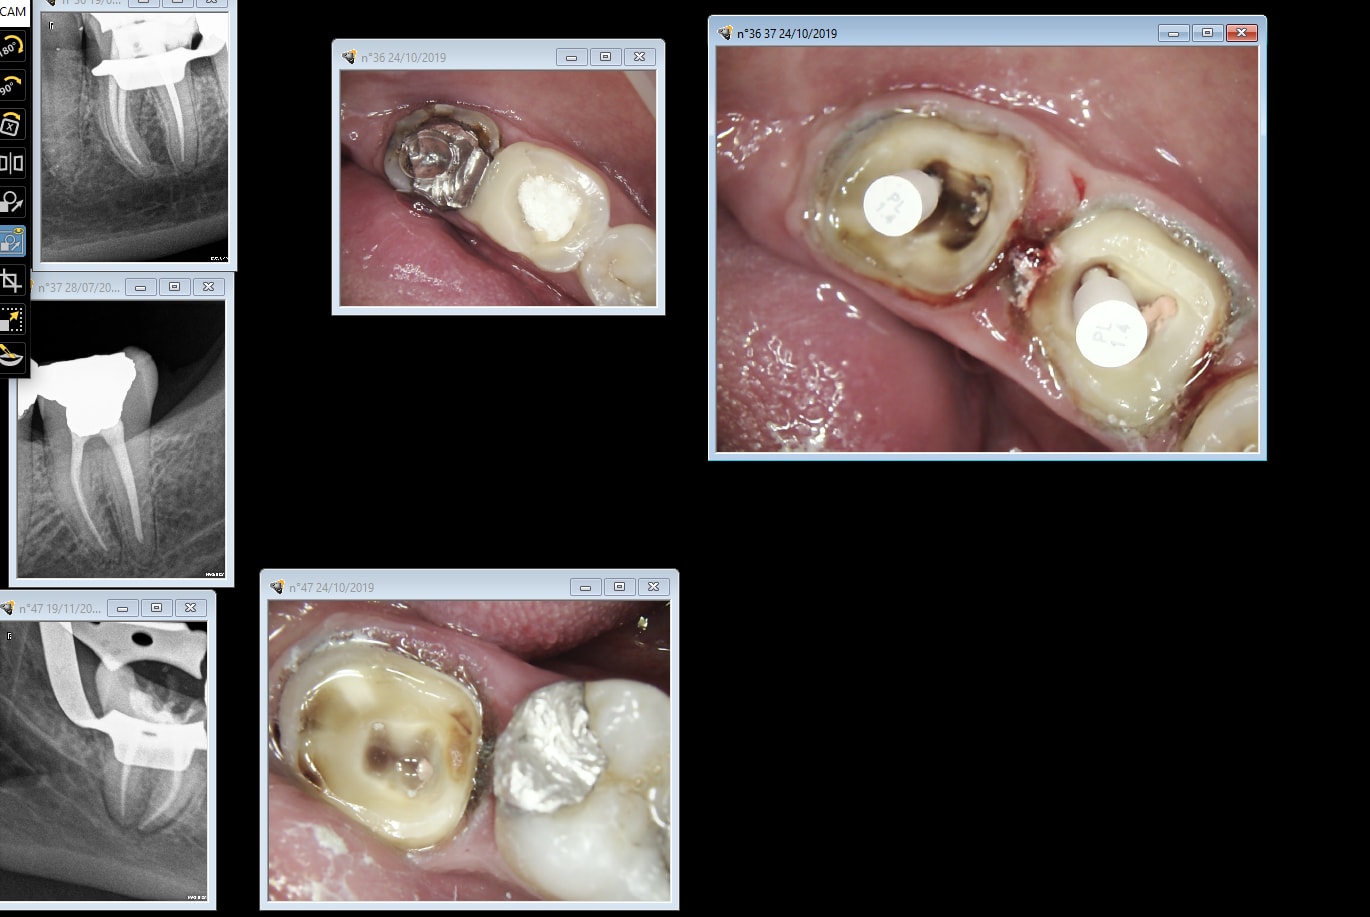

Hum!...

Péri imp kvhkde - Eugenol